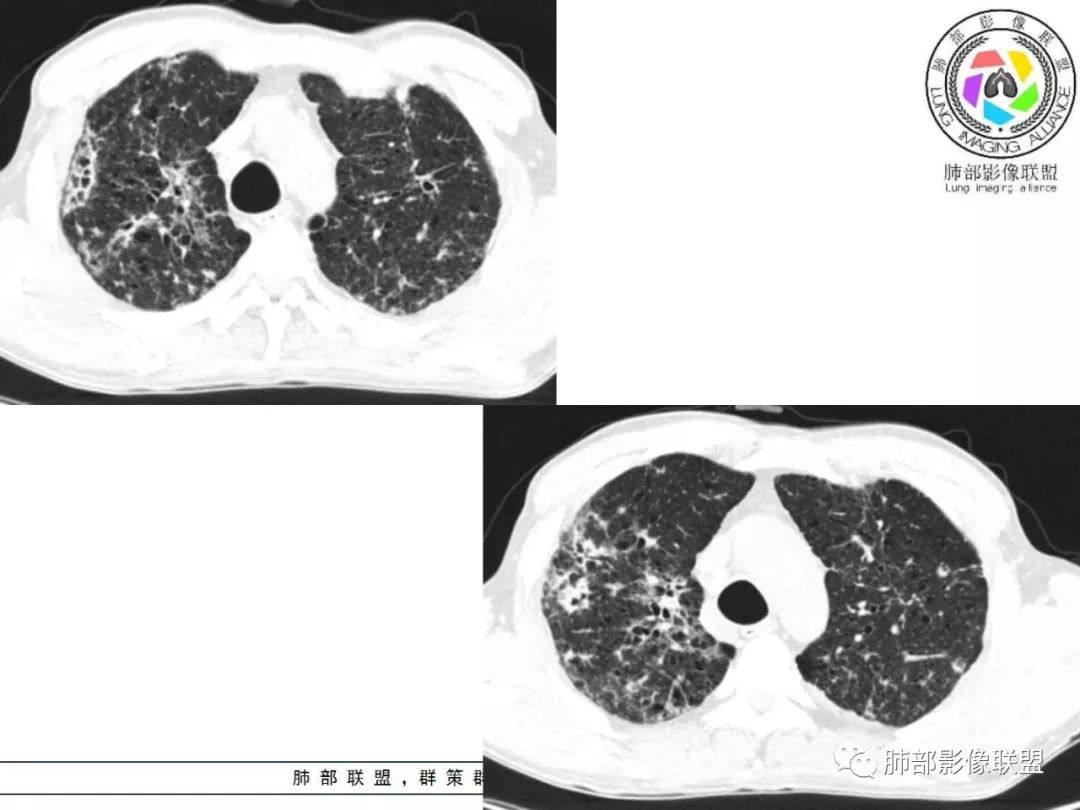

胸部CT:两肺弥漫病灶,磨玻璃影,少许实变,部分累及胸膜,磨玻璃区可见囊?少许胸腔积液,两肺可见结节,支气管血管束增粗,小叶间隔增厚,支气管走形有扭曲扩张,可见纤维化。气肿、大泡。考虑:感染性病变,PCP?查下HIV,CD4,G等。鉴别结核、结缔组织病肺浸润。

两肺肺气肿,弥漫GGO+实变影,局部伴牵拉性支扩,分布无规律。左侧胸膜明显增厚。双肺门淋巴结钙化。

胸部CT:两肺弥漫病灶,中央间质分布为主,部分位于胸膜及叶间裂旁,磨玻璃影,斑片影,部分实性结节,肺气囊,支气管血管束增粗,小叶间隔增厚,叶间裂不均匀增厚,支气管走形有扭曲扩张,可见纤维化、气肿、大泡。考虑:LIP加MALT。鉴别PLCH、PCP、结核、结缔组织病肺浸润。

双肺弥漫性病变,多发磨玻璃密度及小叶间隔增厚,大部分沿支气管血管束分布,伴支气管轻度扩张,以午后及晚上发热为主,考虑感染性病变,间质性结核可能大,另双肺多发肺气囊,LIP待排

中老年男性,双肺弥漫性病变,呈网状、斑片及大片状,实变影及磨玻璃影相间,部分病灶区支气管扩张,并见多发小囊状或蜂窝状透亮影,中央间质增厚,气管前单发小淋巴结。考虑淋巴细胞增生性病变?粘膜相关性淋巴瘤(MALT)或淋巴细胞间质性肺炎(LIP)?鉴别机化性肺炎(OP)及结核(TB)。

两肺弥漫病灶,中央间质分布为主,部分位于胸膜及叶间裂旁,磨玻璃影,斑片影,部分实性结节,肺气囊,支气管血管束增粗,小叶间隔增厚,叶间裂不均匀增厚。考虑:间质性肺病,LIP,鉴别OP

双肺肺气肿背景,双肺弥漫分布磨玻璃及实变密度,病灶沿血管支气管束及胸膜下分布为主,部分病灶以平直收缩为主,局部支气管稍扩张,管壁增厚,小叶间隔增厚,结合临床病史,考虑炎性病灶,感染伴病灶机化?结核?NTM?

中老年男性,发热1月余,双肺弥漫性病变,多发网格、结节、斑片状实变影及磨玻璃影,胸膜下及中轴间质都受累,支气管血管束增粗、变形,支气管扩张,叶间裂及小叶间隔增厚,整体间质性改变明显,考虑结核?OP、LIP?进一步除外PCP、肿瘤、结节病等。

病灶呈片状磨玻璃密度影,呈典型的烟花征。磨玻璃影密度偏高,有网结节样改变,与正常肺实质分界清楚,且常见相对高密度的勾画。

病变一般沿血管支气管束分布或小叶分布,一般上肺多于下肺(这与常见继发性肺结核分布相若)。

2. 肺气肿背景(小叶中心性肺气肿);双肺多发病灶整体沿血管支气管束及胸膜下分布,以上叶及下叶背段分布为主,有实变及GGO,边界清楚,有树芽,小叶间隔及中央间质增厚,叶间裂见到多发结节,部分支气管不规则牵拉扩张,提示病灶纤维化明显,结合临床病史,考虑病灶为间质性感染,肺门及纵隔内有钙化淋巴结,小叶间隔结节,考虑淋巴道增值性疾病可能,综合常规要怀疑间质性肺结核。